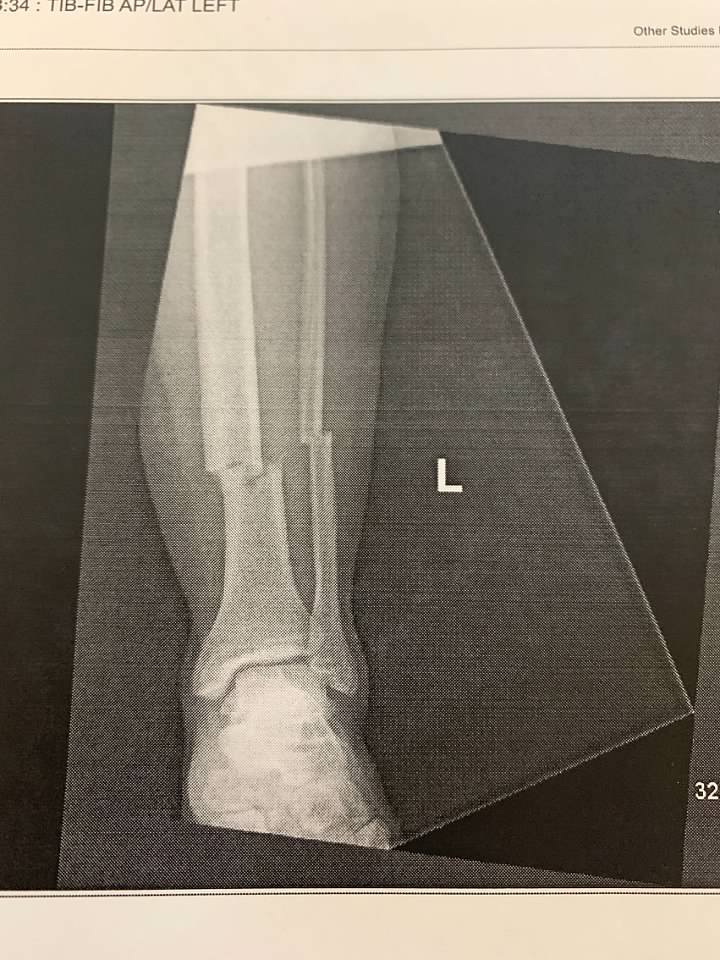

I told him to keep up the hard work and make it to the finish line. I brought to his attention that he has four titanium rods in his legs and two in his back. That's a lot of titanium. I had googled the value of titanium per ounce and it ranges between $0.52 and $10.00 per ounce. I told him that's a lot of money and warned him that if he starts slacking off, I'd sell him for scrap. He laughed and promised me he wouldn't let us down. I know he won't.